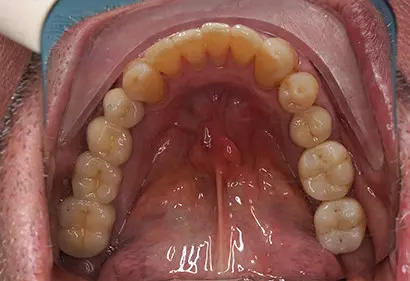

- Протезирование

- Брекеты

- Коронки

- Эстетика

- Лечение